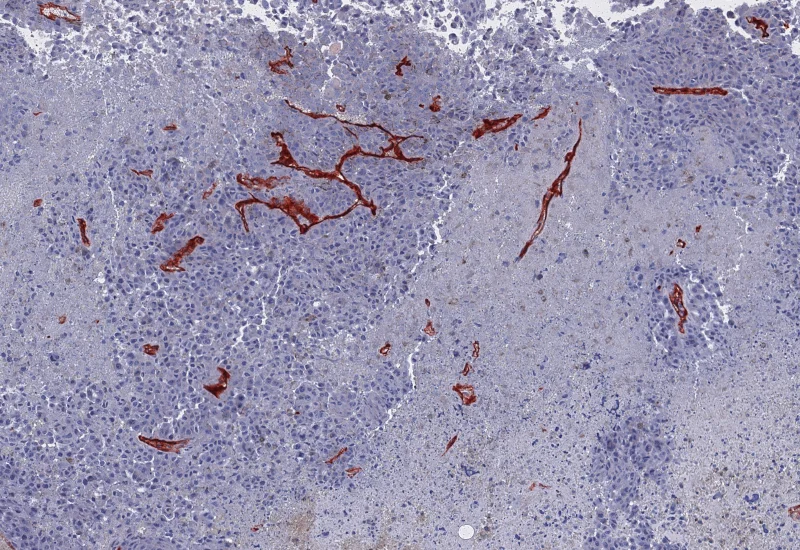

IHC Necrotic Tumor Angio

Segment tumor tissue into tumor, necrotic tissue, and blood vessels using an AI classifier, and quantify compartment areas, total vessel count, and vessel distribution across morphological entities.

The IHC Necrotic Tumor Angio App is able to segment tumor tissues into tumor, necrotic tissue and blood vessels using the AI Classifier. It outputs area of tumor, necrotic tissue and blood vessels as well as the number and percentage of blood vessels in total and within the two morphological entities.

Original Image